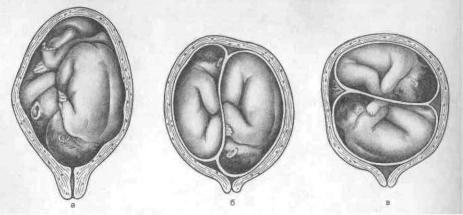

Положення плодів при двійні

При багатоплідній вагітності пологи природним шляхом допускаються в разі, коли в правильному головному передлежанні знаходяться або обидва малюка, або той з них, який повинен з'явитися на світло першим. Якщо ж перший плід знаходиться в тазовому передлежанні, то це, як правило, є показанням до кесаревого розтину. При поперечному положенні хоча б одного малюка з двійні пологи можуть проходити однозначно також тільки оперативним шляхом.

Однак, навіть при відносно сприятливому для пологів положенні плодів в матці, рішення про тактику проведення пологів приймається з урахуванням і інших чинників, які можуть вплинути на перебіг родового процесу.